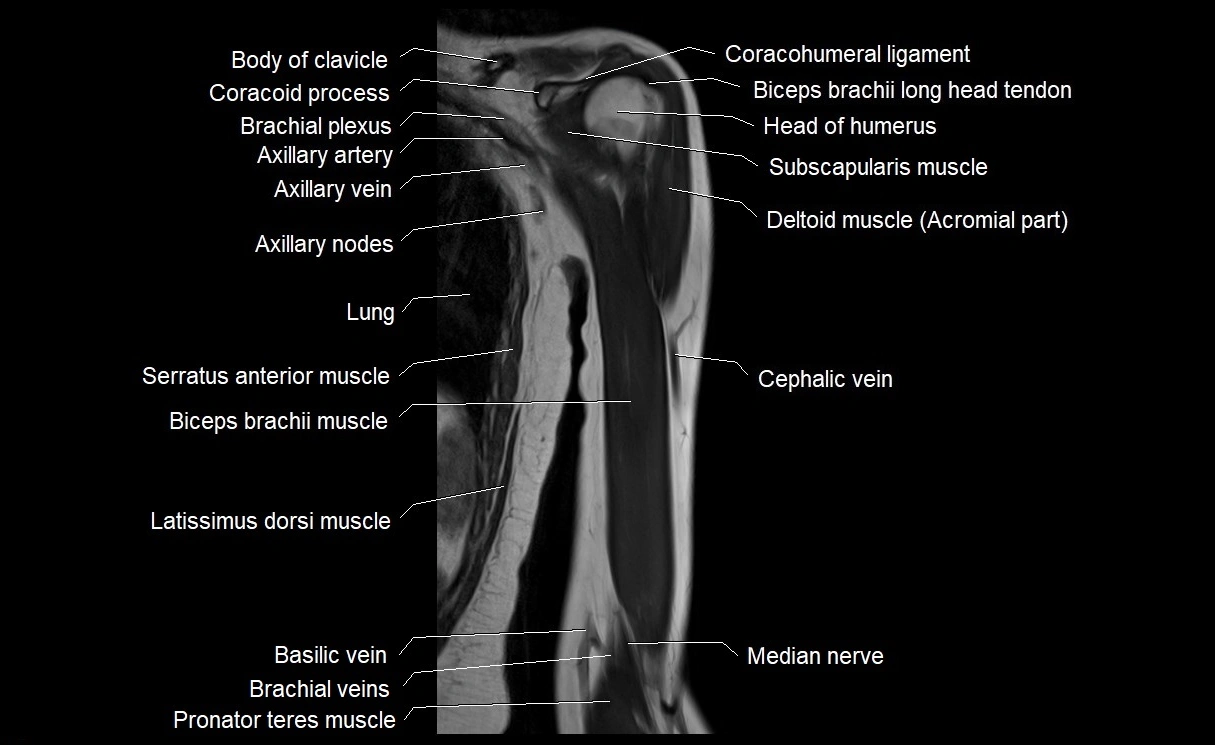

- Biceps brachii muscle

- Cephalic vein

- Median nerve

- Pronator teres muscle